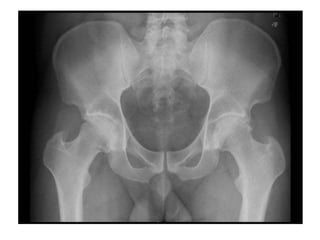

SÍNFISES As superfícies articulares dos ossos cobertos por uma camada de cartilagem hialina, disco fibrocartilaginoso, característica distintiva da sínfise. A articulação entre os ossos púbicos e a articulação entre os corpos.

SÍNFISES As superfíciesarticulares dos ossos cobertos por uma camada de cartilagem hialina, disco fibrocartilaginoso, característica distintiva da sínfise. A articulação entre os ossos púbicos e a articulação entre os corpos.